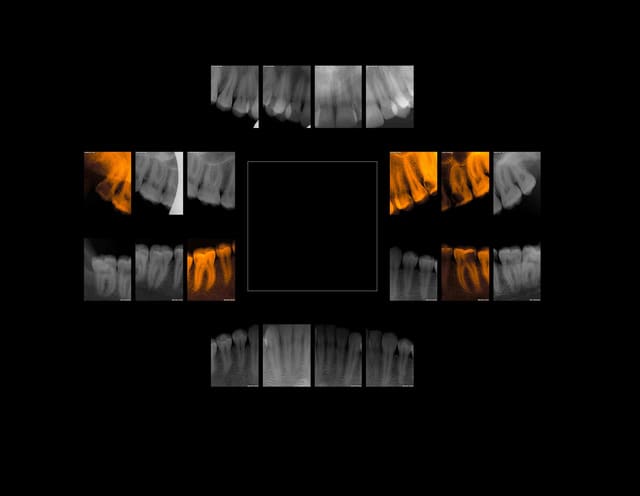

9h .Premier status de la semaine (Z56) Mouarf ! Melanie 28 ans nouvelle patiente CMU (futur emploi d'avenir).

Vos plans de tt svp.

Melanie 28 ans fcf9uu - Eugenol